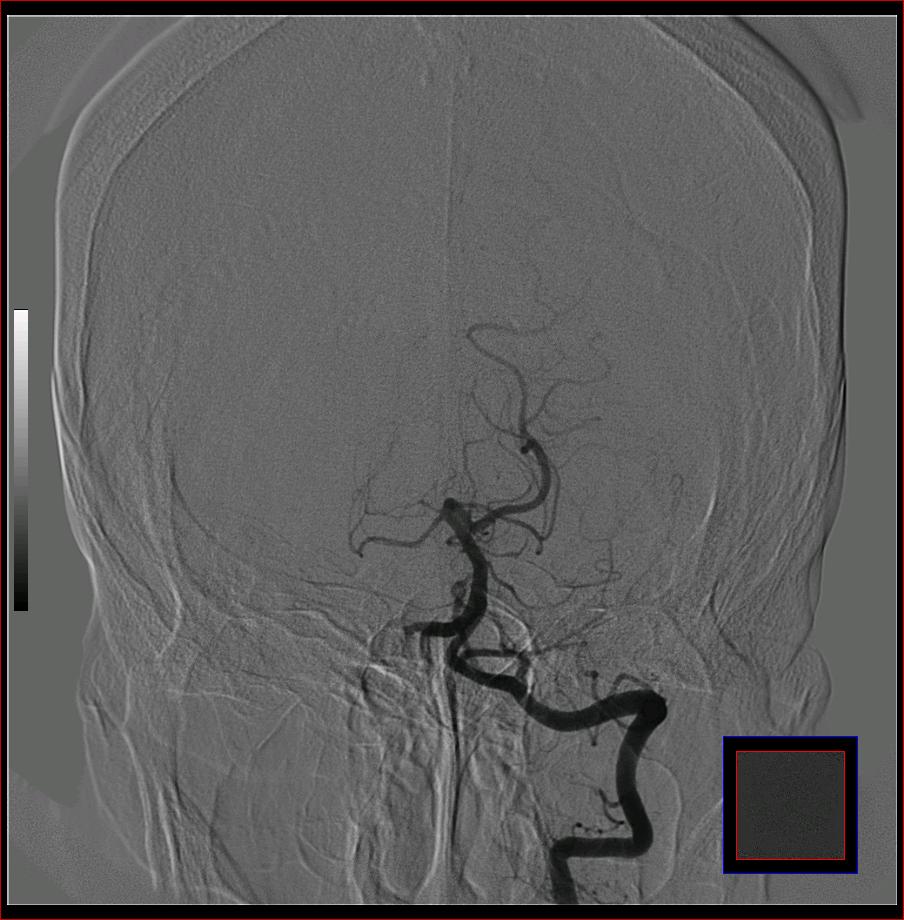

标题: DSA0121:脑血管造影

男,65岁,肢体无力。

大脑前动脉a2段动脉瘤.

右侧大脑前a缺如.左侧大脑中动脉m1段狭窄,远端分支分布稀疏.

右侧大脑前a缺如.左侧大脑中动脉m1段狭窄

前交通或稍远端动脉瘤要仔细查,左大脑中动脉狭窄要鉴别,有可能是痉挛,因为造影导管插得稍深啦。其它就是供血动脉变异较大

烟雾病